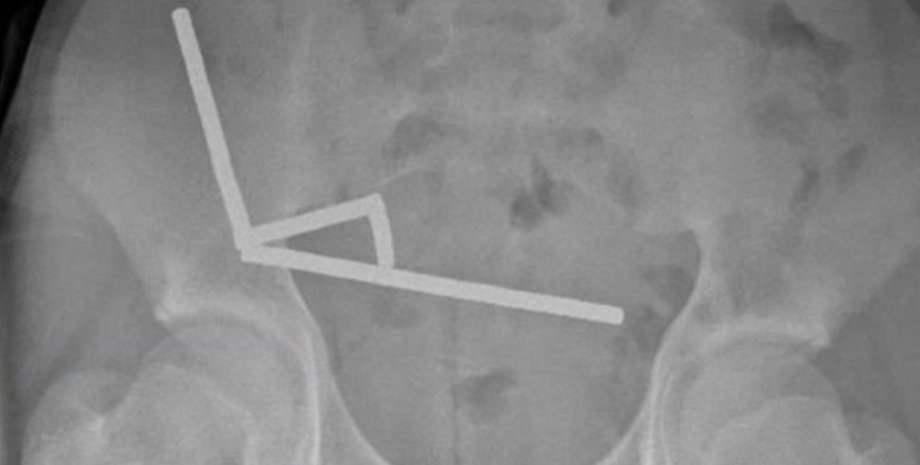

После того, как врачи сделали рентгеновские снимки брюшной полости подростка, они обнаружили, что в разных отделах кишечника мальчика находятся четыре линейных цепочки из неодимовых магнитов, которые соединились. Мелкие металлические предметы соединились, создав разрушительные последствия.

Рентгеновский снимок, на котором видны цепочки магнитов в брюшной полости новозеландского подростка